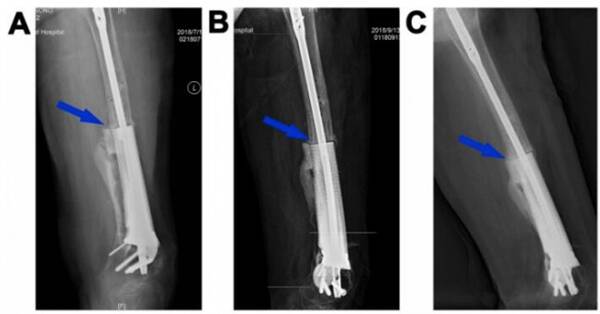

圖5.3D打印多孔Ti6Al4V內(nèi)植物重建股骨缺損(病例2)。末次術(shù)后即刻(A)和植入后2(B)、5個月(C)、8個月(D)、14個月(E)和20個月(F)重建的11cm股骨缺損的X線圖像。藍色箭頭表示內(nèi)植物和宿主骨之間的骨整合。